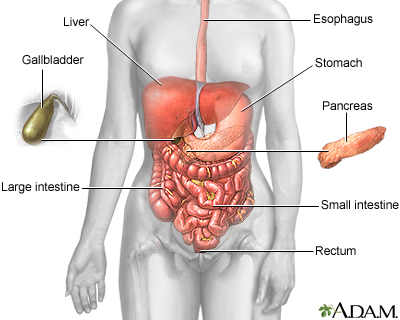

The pancreas is an organ located behind the stomach. It produces chemicals (called enzymes) needed to digest food. It also produces the hormones insulin and glucagon.